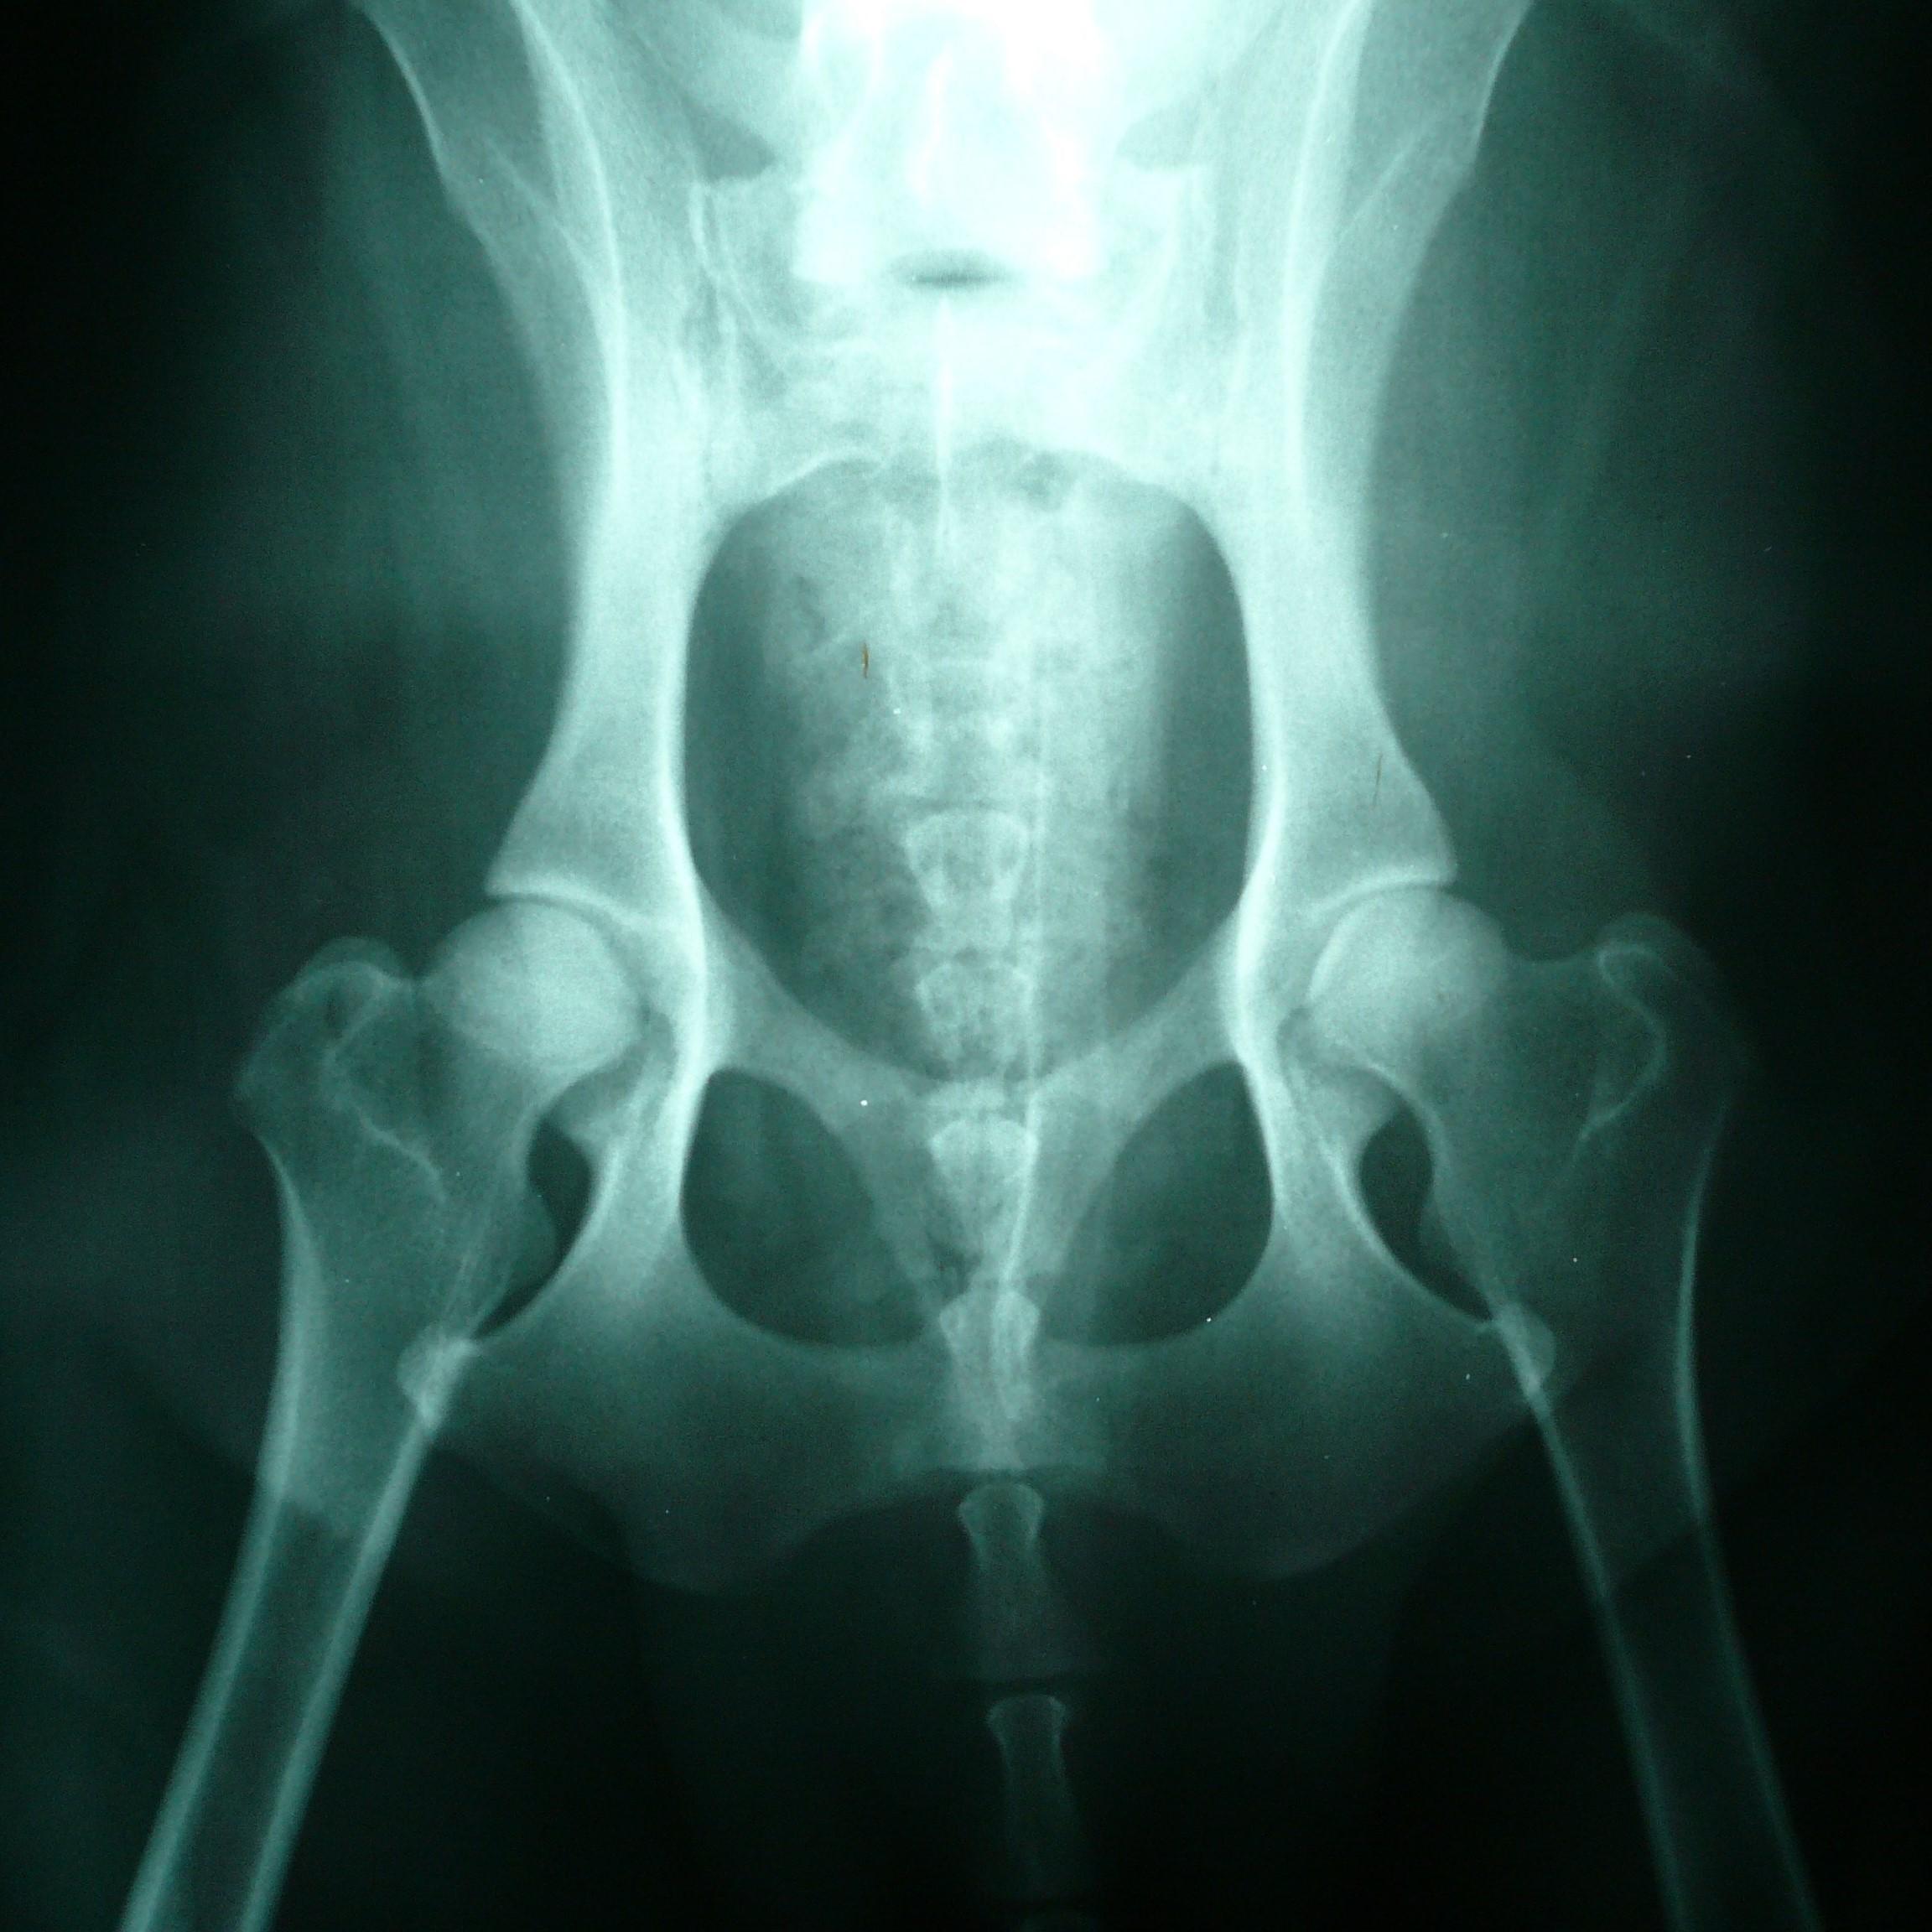

Displasia de cadera, principal causa del fallo en las patas traseras de los gatos

Aunque no es tan habitual como en los perros, existen casos con este padecimiento. Una displasia de cadera en felinos tiende a ser hereditaria y consiste en un desarrollo anormal de los huesos de la cadera y el fémur, que provoca desplazamiento y daño en ambas articulaciones de la cadera o en una sola según cada caso. Este trastorno puede aparecer desde muy pequeño y con el paso del tiempo tiende a dislocarse mucho más ocasionando pequeñas fracturas o daños en los cartílagos de la parte inferior del gato. No obstante, algunas veces puede aparecer cuando el gato es más mayor, por causas que normalmente no son genéticas.

Los síntomas más comunes cuando se presenta de displasia de cadera en gatos son:

• Cojera

• Dolor en las patas traseras

• No salta ni corre

• Crujido proveniente de la cadera

Si además de la debilidad presenta estos síntomas, es importante acudir con el veterinario.